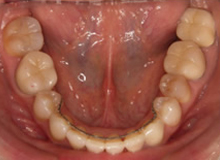

(治療後:写真右)

矯正治療をおこない歯列を整え、金属の詰め物はセラミッククラウンに換えて咬み合わせを再構成しました。

三本の小臼歯を抜歯していますが、歯並びを小さくしないようにしています。

そして矯正治療後、初診時の様々な訴えは解消しました。